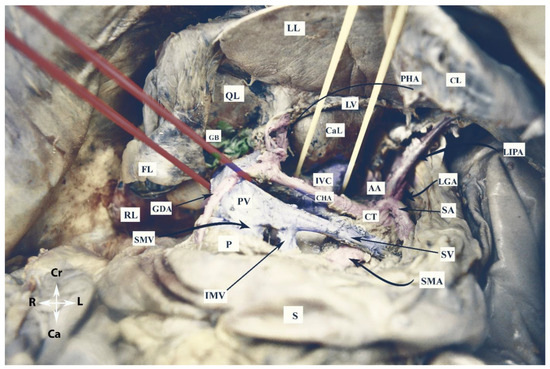

2.1.3. Vessels